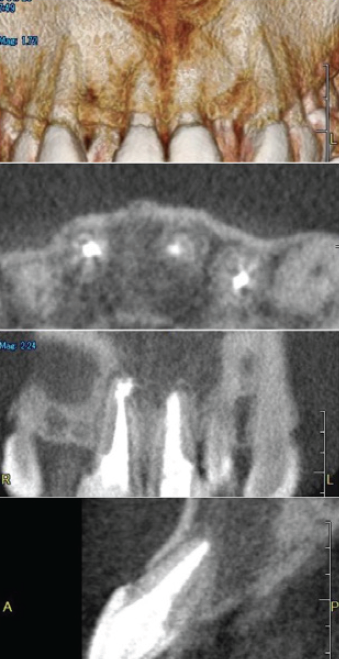

「臼歯部に限局して失活歯が存在し、多発性の根尖病変が認められる症例」

左下大臼歯部の急性炎症を主訴に来院(図16・17・18)。

緊急処置を行い、基礎資料を収集し問題点を抽出し、総合診断治療計画を立案し、患者に説明した。臼歯部に歯科治療が繰り返されている原因の一つに咬頭嵌合位が安定せず、咬合干渉が認められる病的咬合が挙げられる(図19)。臼歯部に応力が集中し、補綴装置やセメントが安定せず歯冠部からの漏洩によって根管内が感染していることも予測できる。包括的な見地から、咬合治療を行うために矯正治療の必要性を説明し承諾を得た。

<術前左下6・7のレントゲン像>

主訴の歯であり、根尖部に広範囲に渡って透過像を認める

歯質は十分に保存されていることが予測される

(図16)

<左下6・7術前CBCT像>

根尖周囲の骨欠損が著明で舌側皮質骨の開窓も予測される

(図17)

<左下6・7術後CBCT像>

術前のCBCT像と比較して

根尖部周囲組織の再生が確認でき、

歯の保存は可能と判断した

(図18)